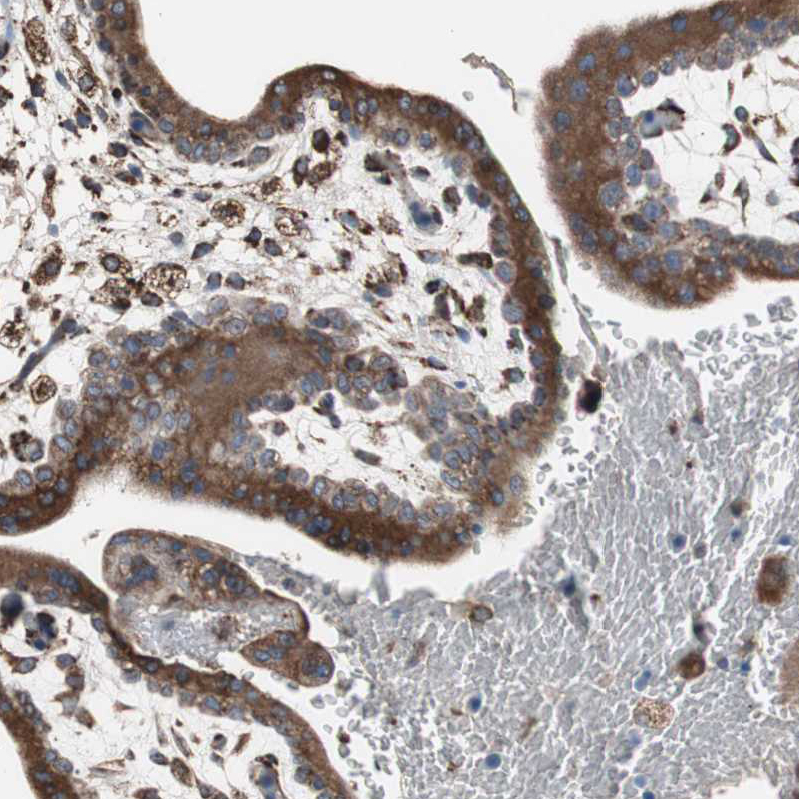

Immunohistochemical staining of human placenta shows strong cytoplasmic positivity in trophoblastic cells.